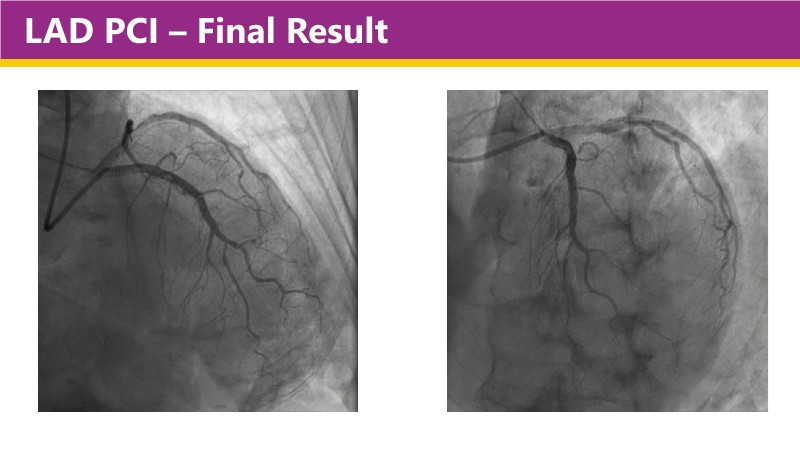

Learn how this technology works, review the supporting evidence, and follow step-by-step case examples demonstrating optimal stent expansion and an efficient calcium modification workflow in daily practice.